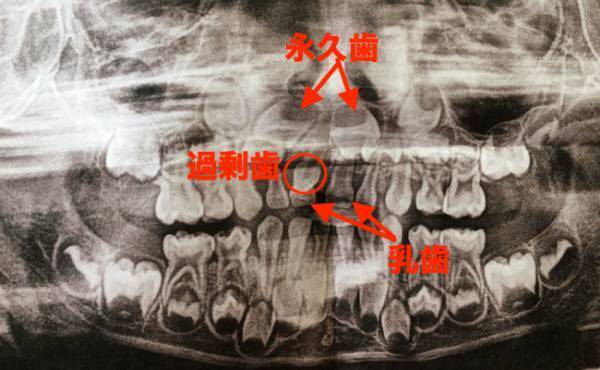

小児歯科へ予約して行くと、「抜歯する際はレントゲンを撮る必要がある」と言われました。口内を診たあとにレントゲンを撮ってもらうと、「白い突起物は永久歯ではなく、過剰歯」と歯科医から言われました。

過剰歯とは字の通り余分な歯で、上の前歯の間にできる例が最も多いようです。また、余分な歯があるせいで歯並びが悪くなる可能性があるとのこと。娘も上の前歯の左側のところに生えてきていましたが、レントゲンを見ると永久歯の前歯の間から斜めに生えているようでした。さらに過剰歯があるために、下の永久歯に比べてかなり歯並びが悪くなっていました。